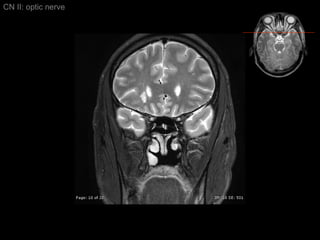

CN II: optic nerve Axial T2/ inferior to superior

CN II: optic nerve